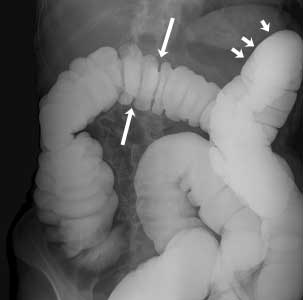

Normal Barium Enema

This image shows a normal colon filled with barium. The barium shows up as white on the image. The arrows point to the normal curves of the colon.